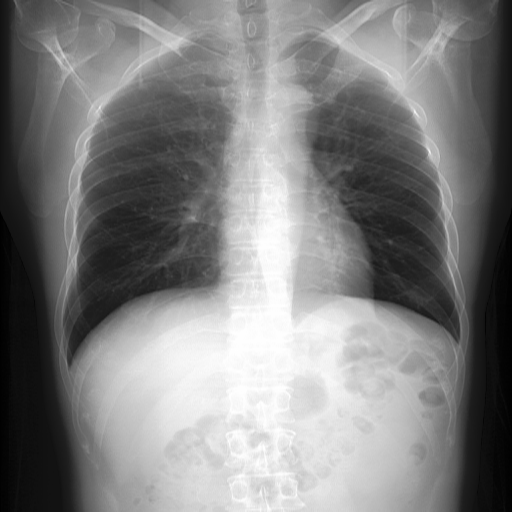

In Fig. 4, we show qualitative examples of the calculation of the cardio-thoracic-ratio for patients presenting cardiomegaly and not presenting cardiomegaly. For the case of the pathology, we see that the border of the heart is expanded, leading to a CTR above 0.7, whereas, for the absence case, the CTR is 0.4255.

When conducting a t-test, we get a value of 139.71 (p-value 0.0001) indicating a strong difference in CTR between positive and negative patients for cardiomegaly. We show this property in the violin plots on the left of Fig. 4, highlighting the CTR distributions for sex, age group, and pathology. Typically, the CTR for the presence and absence of cardiomegaly has noticeable shifts, with both respective means increasing with age. This average increase in CTR, however, becomes less in the age group of , with the disparity in mean CTR between cardiomegaly and no cardiomegaly reducing the older a patient gets. This result, in turn, lessens the insight of CTR with age. We observe this property for male and female patients. On the right of Fig. 4, we show the ROC-Curve for pathology classification based on the CTR score. We see a difference in the diagnostic performance of the CTR for female and male patients with an AuROC of 0.73 and 0.75.

In Fig. 4, we show qualitative examples of the calculation of the SCD for patients for the presence and absence of scoliosis. We can see that the vertebrae segmentation presents a noticeable curvature for the scoliosis case, leading to an SCD above 19, while for the patient with a healthy spine, the SCD is 1.125.

When conducting a t-test, we get a value of 35.30 (p-value 0.0001), indicating a statistically significant difference in SCD between positive and negative patients for scoliosis. On the left of Fig. 4, we show the distributions of the SCD in the form of violin plots for sex, age group, and pathology. Similarly to the CTR, SCD increases with age for the presence and absence of scoliosis. The results show that the older the patient gets, the less the disparity in mean SCD between scoliosis and no scoliosis becomes, indicating that the SCD becomes slightly less insightful the older the patient is. However, different from the CTR, the standard deviation of the SCD is considerably higher, and there is a relatively larger difference in means, leading to a higher predictive value for the identification of scoliosis.